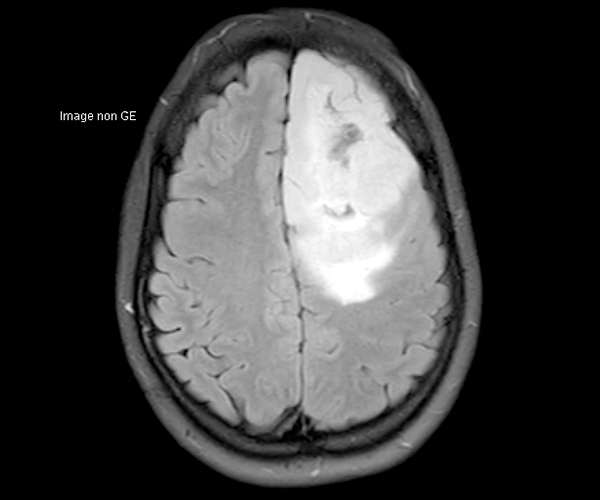

L’amélioration de la résolution spatiale s’applique à l’exploration morphologique des hippocampes dans le diagnostic de la maladie d’Alzheimer, à la détection de petites lésions de sclérose en plaques ou de métastases, à l’étude fine du cortex dans les épilepsies.

L’augmentation de l’effet de susceptibilité magnétique à plus haut champ permet d’améliorer la détection des hémorragies et est utilisé également dans l’imagerie de perfusion (tumeurs) et l’IRM fonctionnelle (BOLD). L’allongement du T1 à plus haut champ entraîne une meilleure saturation des tissus statiques et par conséquent une augmentation du contraste sang/tissus dans l’AngioIRM.